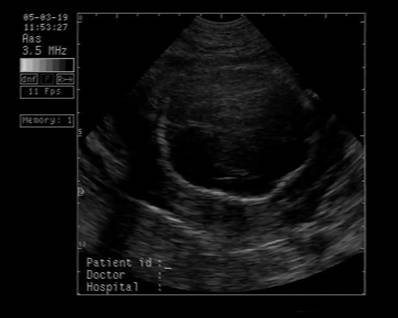

Fig. nr.250. Ciclopie diagnosticata la 17 sapt.